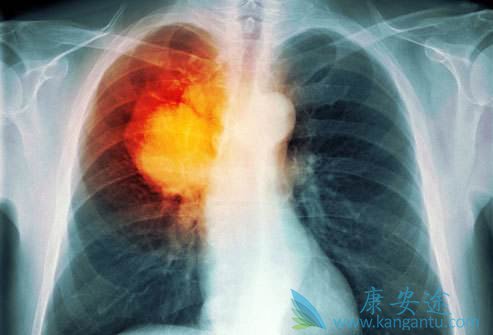

• 肺癌骨转移症状最常见的为疼痛和骨折

肺癌骨转移症状最常见的为疼痛和骨折

肺癌是目前各种肿瘤中发病率和死亡率最高的肿瘤,被称为肿瘤第一杀手。当肺癌发生骨转移,就意味着肺癌已发展到最晚的一期,治疗效果比较差,所以发现肺癌后,应接受专业医师指导,积极恰当地治疗,避免病情进一步发展。 肺癌骨转移症状 有哪些?疼痛是 ...